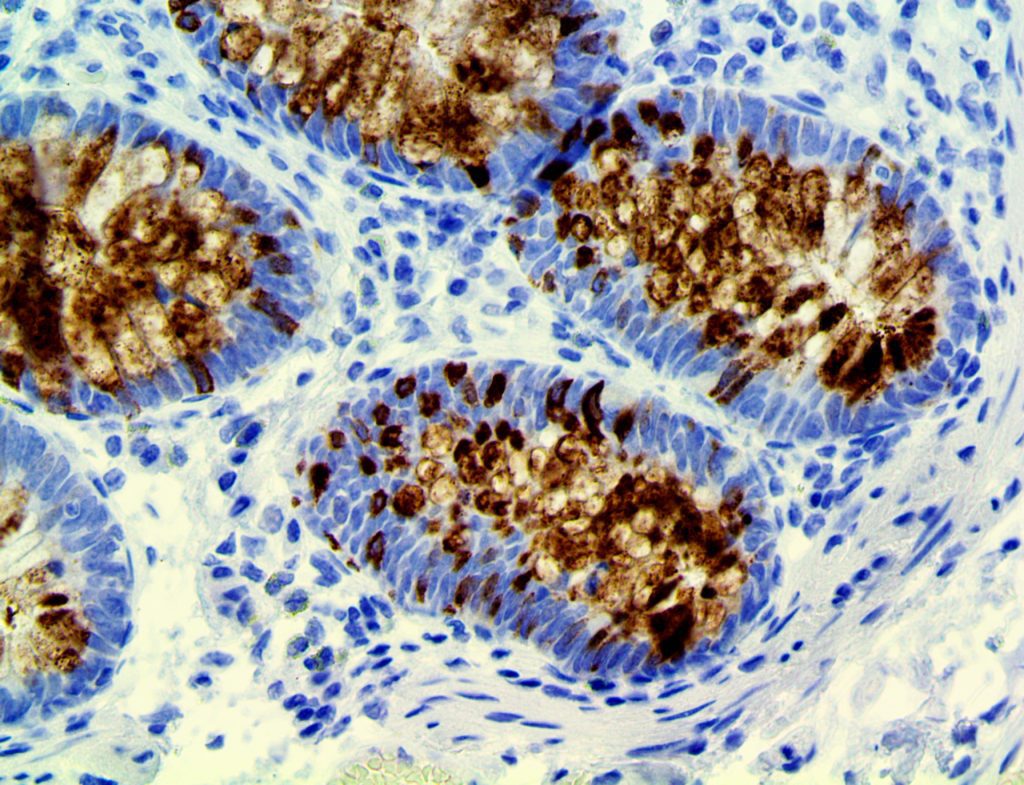

It is the ICU physician who is most likely to witness one of the deadliest manifestations of the abnormal immunological response, the cytokine storm syndrome (CSS). This response is also referred to by some as the cytokine release syndrome (CRS). CSS is characterized by continuous activation and expansion of macrophage and lymphocyte populations, which secrete large amounts of cytokines, causing the cytokine storm. This massive cytokine release is akin to hemophagocytic lymphohistiocytosis (HLH) disease, a syndrome characterized by initial unchecked and persistent activation of cytotoxic T lymphocytes and NK cells.

Clinical and laboratory manifestations of HLH include fever, enlarged liver and/or spleen, neurologic dysfunction, coagulopathy, liver dysfunction, cytopenias (i.e., low levels of erythrocytes, leukocytes, and/or platelets), hypertriglyceridemia, hyperferritinemia, hemophagocytosis, and eventually diminished NK cell activity as the immune system becomes progressively paralyzed. HLH can be familial (primary HLH) or secondary to another disease process (sHLH), such as rheumatic disease, in which it is referred to as macrophage activation syndrome (MAS, characterized by elevated ferritin).

This activation induces inflammatory monocytes to highly express IL-6, starting a localized and then systemic cascade effect that results in hyperproduction of IL-6, which accelerates the inflammatory process. Because IL-6 also increases vascular permeability, excessive levels cause blood vessels to become very leaky. This, along with clotting factors released from vascular endothelial cells, stimulates the coagulation cascade, resulting in microthrombosis (tiny clots), which leads to ischemia and tissue death of the kidney, intestines, heart, liver, brain and extremities.